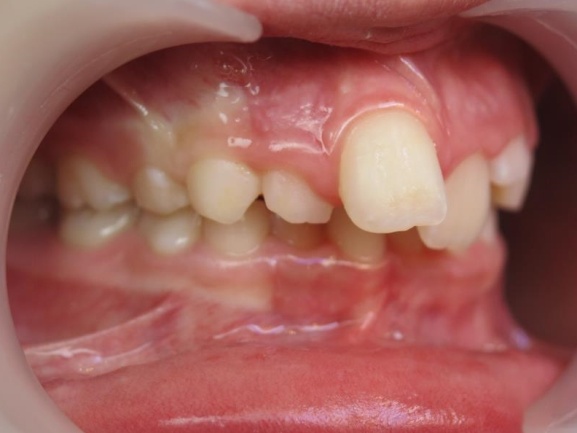

1 - Avant et après traitement

Un traitement orthopédique a permis d’optimiser la croissance des bases osseuses, offrant des conditions favorables à l’évolution de la dentition. Le traitement multiattaches a ensuite aligné les dents sur des structures squelettiques correctement développées.